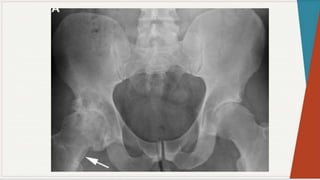

Radiografia Simples:

◗ Incidência ântero-posterior:

observar

as

características: espaços

articulares e

linhas

seguint

es

pélvica

s,

presença de qualquer doença óssea, ângulo colo-

diafisário, forma da cabeça femoral, presença de

osteófitos, evidência de fratura ou luxação,

evidência de deformação pélvica.

Radiografia Simples: ◗ Incidênciaântero-posterior: observar as características: espaços articulares e linhas seguint es pélvica s, presença de qualquer doença óssea, ângulo colo- diafisário, forma da cabeça femoral, presença de osteófitos, evidência de fratura ou luxação, evidência de deformação pélvica.